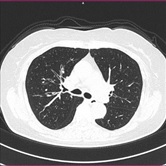

胸部CT画像 腹部CT画像

CT検査には、そのまま検査台に寝ていただき撮影する単純CTと造影剤を用いた造影CT検査があります。基本的には単純CT検査を行った後、より詳細に観察したい場合や血管などを観察する場合に行います。造影CT検査は肘(ひじ)のあたりに針を刺し血管内(静脈)に造影剤を入れて撮影します。

単純CT画像 造影CT画像 MPR画像